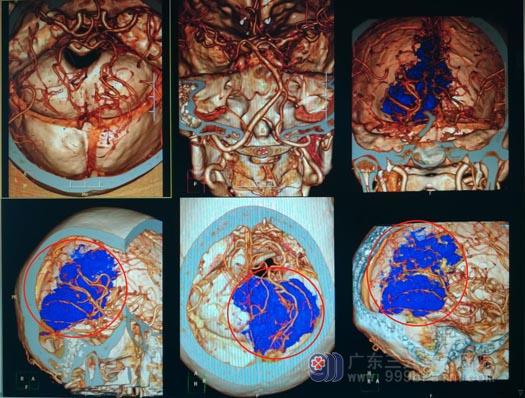

▲术前CTA

在神经外五科,科室治疗团队进行了多次讨论并制定了缜密的手术方案。肿瘤巨大,血供非常丰富,直接去切肿瘤无疑会出血较多,增加手术困难,也增加患者创伤。手术当天先进行肿瘤供血血管造影,精准了解肿瘤的血供来源,并完成部分血管的封堵。然后由鲁明主刀行肿瘤切除术,肿瘤体积大,血管来源多,并且肿瘤直接侵犯破坏大静脉,打开颅脑后脑压较高,切除部分枕叶后暴露出肿瘤,肿瘤起源小脑幕及大脑镰,侵犯直窦,为彻底切除窦内肿瘤,予以结扎直窦;肿瘤右侧顶枕部为主,突入松果体区及对侧,挤压胼胝体毗邻大静脉。耗时3个小时将肿瘤彻底切除,脑神经及重要血管保护良好。